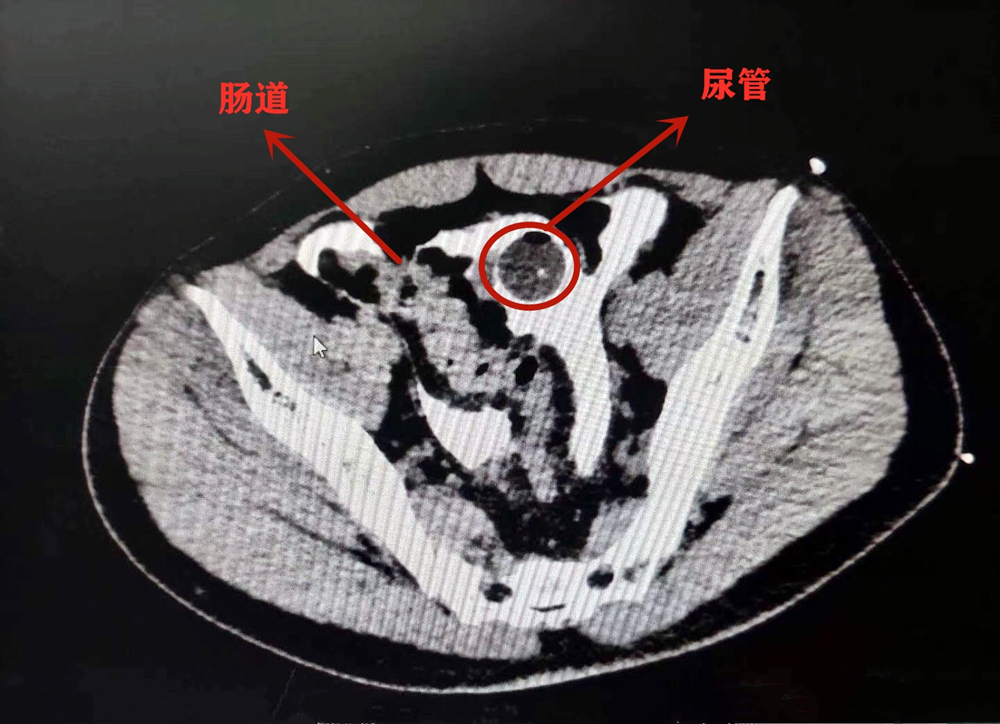

辗转几家医院,小李在26日晚上被送到了成都市第三人民医院。该院泌尿外科副主任医师袁仁斌博士说,小李膀胱有一个4*3cm的破洞,尿管也顺着洞“跑”到了腹腔内,因为尿液在腹腔内蓄积了很长时间,已经引发了比较严重的腹膜感染,“如果再不及时手术,可能生命都会受到威胁。”

当晚,小李便接受了修补手术。好在,经普外科医生接力探查,发现他腹腔内的其他脏器未受到伤害。经进一步康复,小李即可出院。